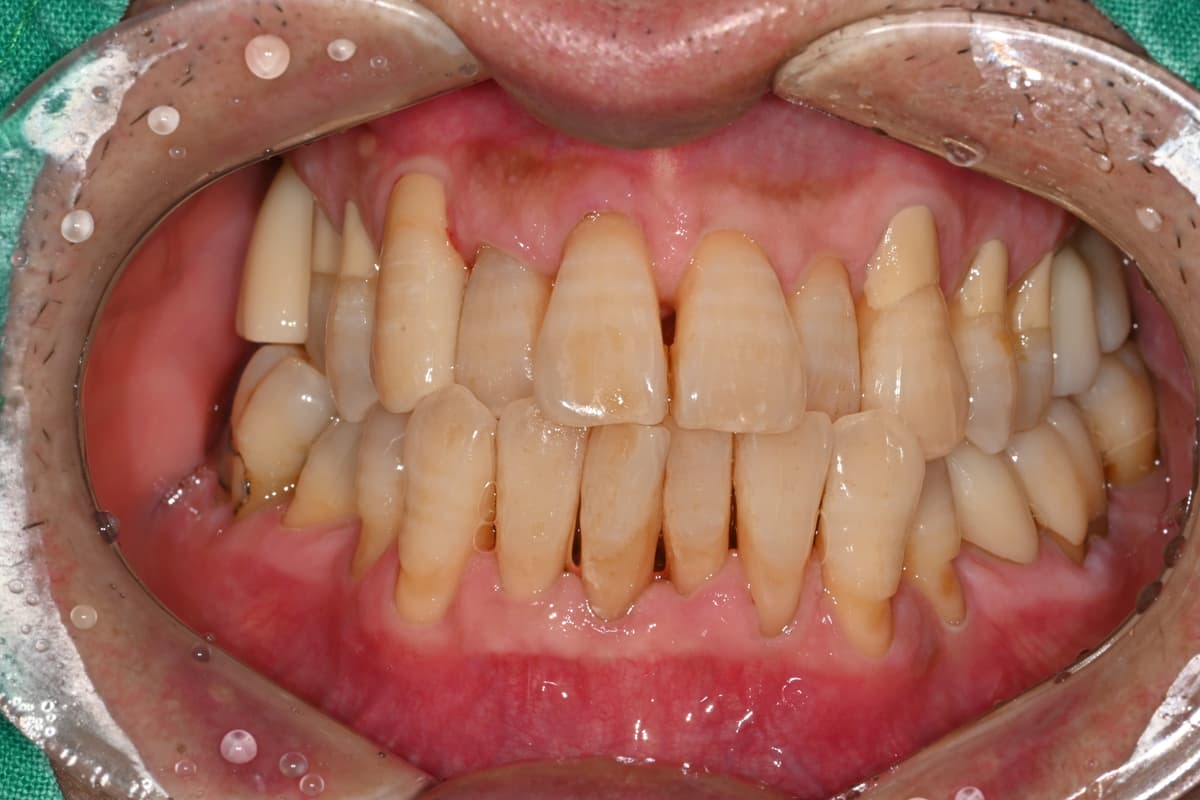

"Suyak juda ko'p yemirilgan edi,

milk davolash orqali suyak tiklanib ketdi"

Before

After

Og'ir milk kasalligi tufayli suyak ko'p yemirilgan holat

Milk davolash va suyak ko'chirish orqali suyak tiklanib, implant muvaffaqiyatli o'rnatildi